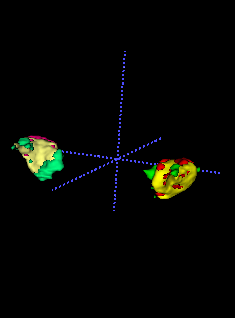

To model , we propose using a half-Gaussian distribution based on nodule size distribution because is correct if it is within the nodule area (center slice of as , and nodule size can be empirically estimated based on existing data) for nodule detection in Fig. 17(a). For lung lobe prediction , a logistic regression model is used based on relative value of nodule center after lung segmentation. That is

| (22) |

where is the associated weights with lobe location for logistic regression, feature , and is the total size of image after lung segmentation. In the experiments, we found the logistic regression converges quickly and is stable.